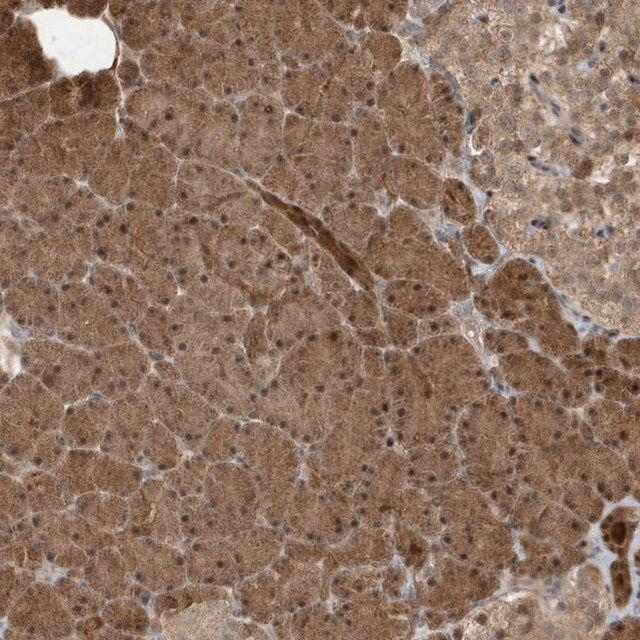

| technique(s) | immunofluorescence: 1:50-1:200 immunohistochemistry: 1:50-1:200 western blot: 1:500-1:2000 |